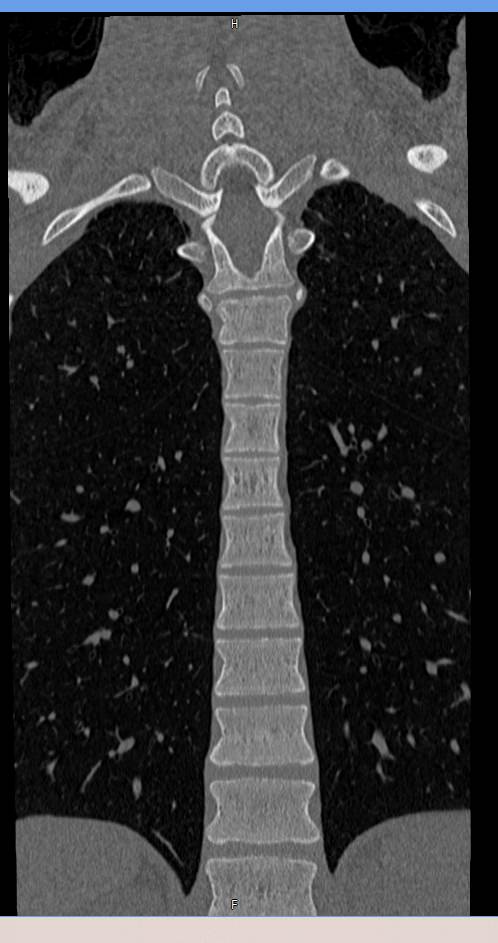

Мультиспиральная компьютерная томография – это современный быстрый и точный способ диагностики заболеваний позвоночника, основанный на использовании рентгеновского излучения. Метод позволяет получать послойные изображения грудного сегмента позвоночного столба, включая 12 грудных позвонков, задние отрезки ребер, межпозвоночные диски, позвоночный канал.

При помощи инновационных компьютерных программ данные преобразуются в трехмерные изображения позвоночного столба с сосудами, нервами и лимфатическими узлами в мельчайших подробностях. Наглядные объемные 3D-изображения высокого качества помогают в диагностике различных заболеваний позвоночника и бывают особенно полезны при планировании хирургических операций, при оценке эффективности проведенного лечения.

Что показывает компьютерная томография грудного отдела позвоночника

- изменения структуры и расположения позвонков и окружающего их мышечно-связочного аппарата

- аномалии развития позвоночника

- травмы позвоночного столба (переломы и трещины)

- ширину спинномозгового канала

- признаки наличия межпозвоночной грыжи (протрузии, экструзии)

- абсцессы, туберкулёзное поражение, новообразования, наличие метастазов и прорастание опухолей из соседних органов

- изменения в спинном мозге (кровоизлияния и др.)

- дегенеративные изменения

- участки пониженной плотности кости — остеопороз при визуальной оценке